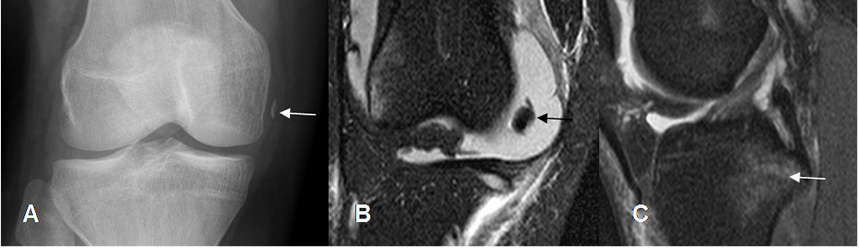

Fig 40 A. Fractura de Segond.

A: Rx AP. Fragmento óseo por encima de la cabeza del peroné, paralelo al borde del platillo tibial, que corresponde a fractura de Segond.

B: RM coronal en STIR. Contusión asociada del cóndilo femoral y platillo tibial lateral.

C: RM sagital en STIR. Este tipo de lesión se asocia con ruptura del LCA.